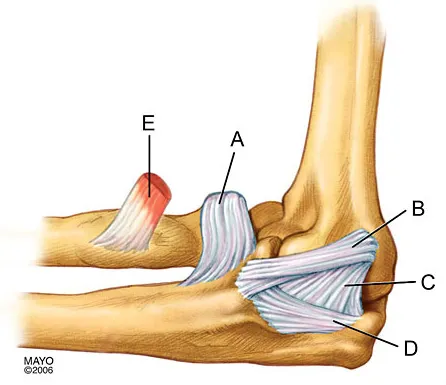

The medial collateral ligament complex of the elbow originates on what portion of the medial epicondyle?

Explanation

Question 85High Yield

In Figure 2, which of the following structures is the primary stabilizer in preventing valgus instability of the elbow?

Explanation